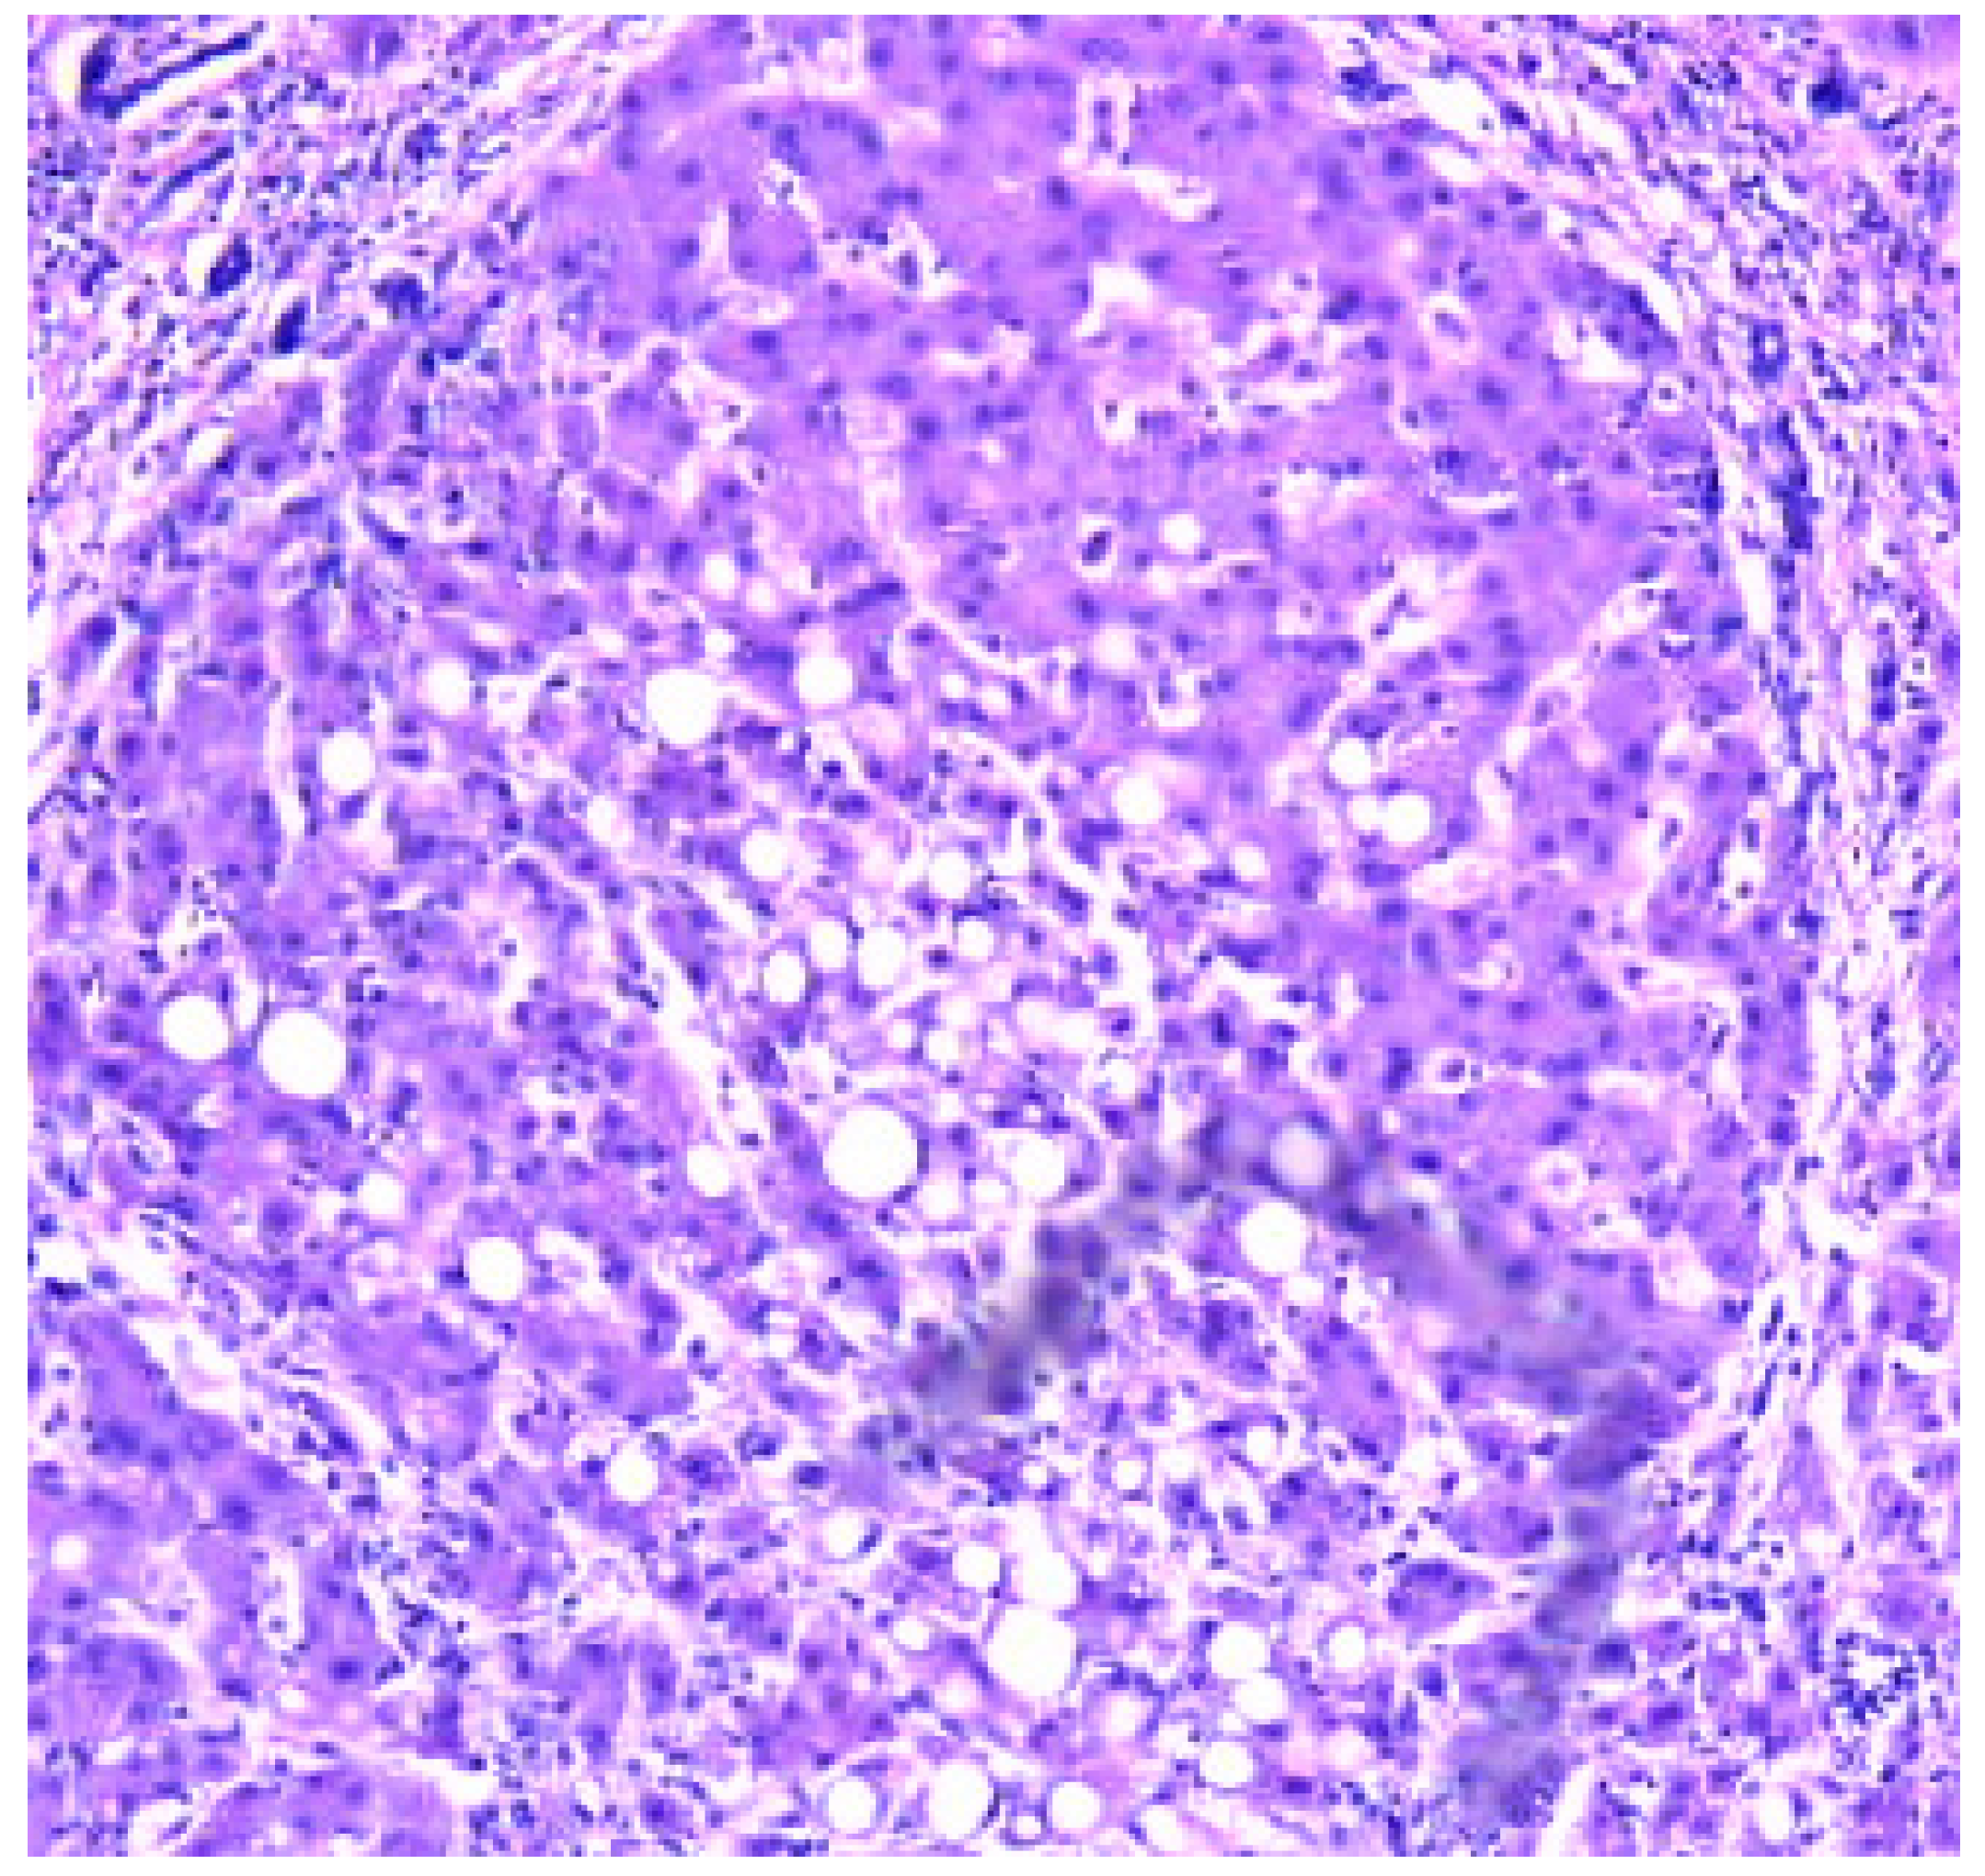

- Zone I is considered to be the periportal region of hepatocytes and are the best perfused and first to regenerate due to their proximity to oxygenated blood and nutrients. Implication in oxidative metabolisms.

- Zone II is defined as the pericentral region of the hepatocytes.

- Zone III has the lowest perfusion due to its distance from the portal triad. Implication role in detoxification.